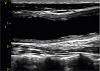

An 18-year-old man was admitted to our department because of arm claudication and right carotidynia. Physical examination revealed loud bruits over the carotid arteries bilaterally and asymmetrical upper limb blood pressure and pulses. Laboratory data showed microscopic anemia along with elevated ESR and CRP at 64 mm/h and 192 mg/L, respectively. Doppler ultrasonography of the neck revealed a long homogeneous, midechoic, circumferential wall thickening of both common carotid arteries (Figures 1 and 2). The Intima-media thickness of the right common carotid artery was 0.17 to 0.26 cm (the maximal normal value is 0.06 cm). This elementary ultrasound lesion, known as “macaroni sign”, is almost pathognomonic of Takayasu arteritis (TA).1) Computed tomography angiography of the aorta and its major branches showed a circumferential mural thickening of the thoracic and abdominal aorta. Furthermore, we noted high-grade stenosis of the following vessels: left subclavian artery, both renal arteries, and both superior and inferior mesenteric arteries.

Although angiography is the gold standard in the diagnosis of TA, it usually misses arterial wall changes particularly in early stage of the disease. On the other hand, ultrasonography is a non-invasive and valuable tool for the diagnosis of early TA; it delineates artery wall swelling which is circumferential, long, and homogeneous. Moreover, ultrasonography is also used to monitor disease activity during the follow-up of patients with TA.